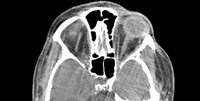

KÖLN. Was tun, wenn ein Aneurysma durch Zufall entdeckt wird? „Mit unseren modernen Bildgebungsverfahren lässt sich diese Gefäßaussackung der großen Hirngefäße am Hirnstamm heute viel früher und leichter diagnostizieren. Nicht selten tritt ein Aneurysma zutage, wenn wegen ganz anderer Beschwerden eine Aufnahme vom Gehirn mit Computertomographie oder Magnetresonanztomographie gemacht wird. OP ja oder nein, lautet dann die Frage, mit der sich Arzt und Patient auseinandersetzen müssen. Sie muss immer im Einzelfall und ganz individuell beantwortet werden“, betont Prof. Dr. med. Veit Braun, Chefarzt der Neurochirurgie am Diakonie Klinikum Jung-Stilling in Siegen. Der Facharzt bewertet ein behandlungsbedürftiges Aneurysma anhand seiner Größe, seiner Form und seiner anatomischen Lokalisation.

Wird ein Aneurysma zufällig entdeckt, steht die Risikoeinschätzung im Vordergrund. Wie groß ist die Gefahr einer Blutung im Vergleich zur Gefahr, die von einem Eingriff am Gehirn ausgeht? „Wir betrachten dabei jeden Patienten im Einzelfall. Wird ein Aneurysma zum Beispiel bei einem eher jungen Patienten entdeckt, hat dieser statistisch gesehen ein größeres Risiko, dass sein Aneurysma im Lebensverlauf platzt. In die Bewertung seines individuellen Risikos muss neben der Größe und der Form des Aneurysmas auch die wahrscheinliche Lebenserwartung einbezogen werden. In der Kombination aller Faktoren lässt sich abschätzen, welche Therapie die richtige ist“, schildert Neurochirurg Prof. Dr. med. Veit Braun. Für die operative Behandlung eines Aneurysmas kommen zwei Verfahren, das Coiling und das Clipping in Frage. Beide Operationsverfahren werden im Diakonie Klinikum Jung-Stilling in Siegen in einem modernen Hybrid-OP durchgeführt. Hier können Aneurysma Patienten besonders schonend mit Unterstützung moderner Technik behandelt werde.